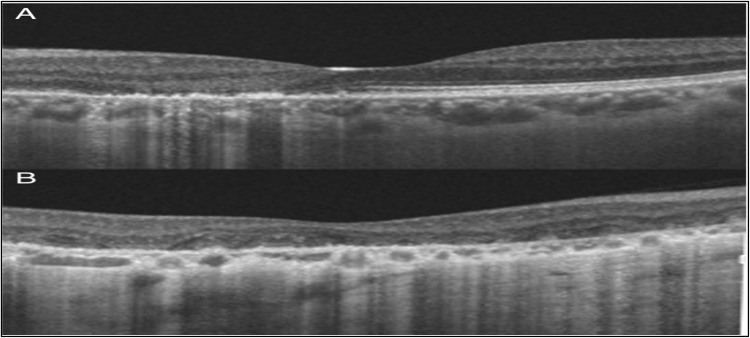

Case presentation: A 42 year old woman with steadily declining vision in her right eye for the previous four months presented to the emergency department. On the Snellen chart, the best-corrected visual acuity was 20/28 in the left eye and 20/100 in the right eye. The intraocular pressure (IOP) of the right and left eyes was 15 and 16 mmHg, respectively. Anterior segment examination was unremarkable. Fundus examination of the right eye revealed a gray finger-like lesion with an active border. The left eye showed a small yellowish-finger-like lesion involving the nasal macula. Disruption in the ellipsoid zone in the right eye and the parafoveal region in the left eye was demonstrated using optical coherence tomography (OCT). Fundus fluorescein angiography revealed bilateral, finger-like branching lesions were seen on fundus fluorescein angiography (FFA). Fundus Autofluorescence (FAF) showed hypoautofluorescence lesions with hyper-autofluorescence edges. Both eyes were diagnosed with active serpiginous choroiditis, after excluding any active infections through blood work-up. The patient was started oral prednisolone 0.5 mg/kg tapering; however, because the patient would be traveling for three weeks, the systemic oral steroid with an intravitreal dexamethasone implant in each eye. After nine days, there was noticeable improvement in the visual acuity of the right eye with normal intraocular pressure. OCT showed minimal restoration of the ellipsoid zone in the right eye, with resolved inflammatory material in both eyes (Figure 1). After starting Azathioprine, disease activity was suppressed for six months without relapsing.